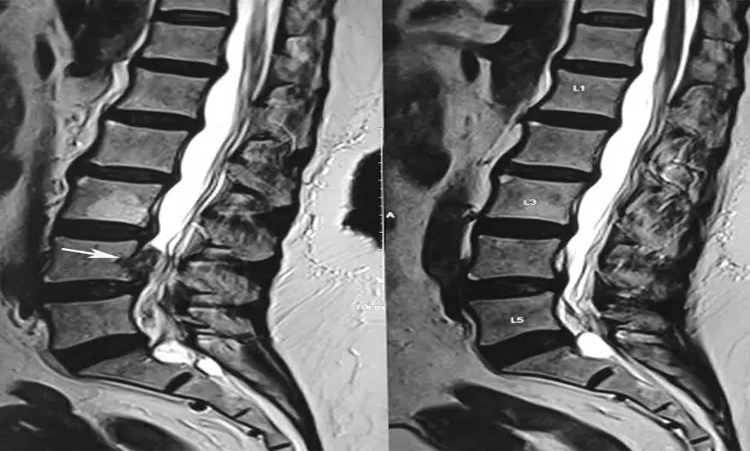

خواندن تصاویر ام آر آی نیاز به درک عمیق از آناتومی ستون فقرات و دیسکهای بینمهرهای دارد. تصاویر ام آر آی معمولاً به صورت مقاطع افقی، عمودی یا مایل از ناحیه کمر ارائه میشوند. در هر تصویر، پزشک باید به دنبال تغییرات غیرطبیعی در بافتها، مانند ورم، هرنی دیسک یا تغییرات دژنراتیو باشد. آشنایی با ساختارهای آناتومیکی، مانند مهرهها، دیسکها و عصبها، به پزشکان کمک میکند تا تغییرات را بهتر شناسایی کنند.

در تفسیر تصاویر ام آر آی، پزشکان باید به جزئیات دقیق توجه کنند. به عنوان مثال، در هرنی دیسک، ممکن است بخشهایی از دیسک به سمت خارج فشار بیاورند که میتواند به عصبها آسیب بزند. این نوع تغییرات در تصاویر به صورت برجستگی یا افتادگی دیسک مشاهده میشود. همچنین، علائم دیگری مانند تنگی کانال نخاعی، که ممکن است به دلیل بزرگ شدن لیگامانها یا دیسکها ایجاد شود، باید در نظر گرفته شوند. شناخت این علائم و نشانهها برای تشخیص صحیح ضروری است.